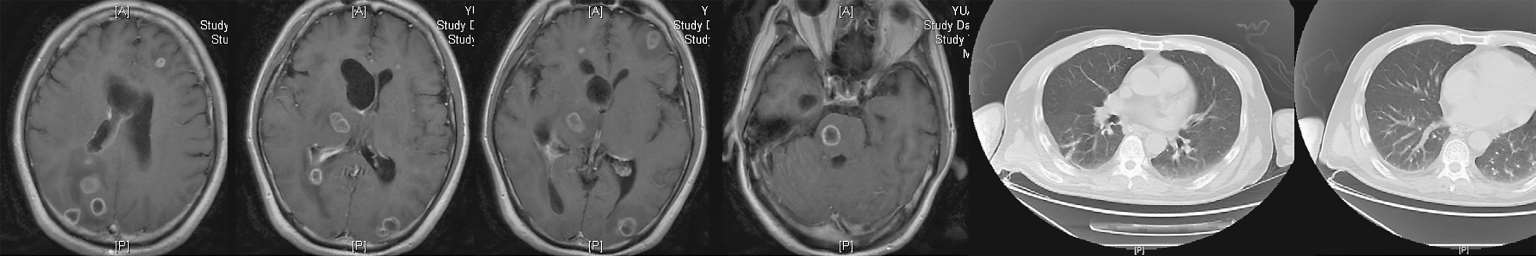

7月30日患者行上腹部增强CT(图2-6),发现肝脾的低密度影已几近消失不见,但回报左肾占位性病变,考虑肿瘤可能。7月30日复查血T-SPOT. TB 仍为阴性。入院治疗两周后8月3日复查腰穿,压力220 mmH 2 O,脑脊液白细胞344×10 6 /L(↑),多核细胞32%,单核细胞68%,脑脊液糖2 mmol/L( ↓),同步血糖5.8 mmol/L,脑脊液蛋白质4 543 mg/L(↑),脑脊液氯106 mmol/L(↓)(表2-1)。脑脊液隐球菌荚膜抗原乳胶凝集试验及培养仍为阴性。此次脑脊液白细胞及蛋白质较前进一步升高,糖进一步下降。虽然此时患者体温已降至正常,但8月7日复查头颅增强MRI(图2-7)见颅内多发异常环形强化灶,部分病灶较前似有所增大,肺部CT平扫却见肺部病灶较前明显吸收减少。同时8月7日第二次脑脊液二代测序回报再次测得中间链球菌,序列数106。

图2-7 2018年8月7日头颅增强MRI及肺部CT平扫

8月22日复查头颅及胸腰椎增强MRI示病灶均较前明显好转(图2-8)。患者已能对答切题及按照指令动作,GCS评分15分,拔除胃管后可自行进食。8月23日,调整方案为头孢曲松2 g ivgtt q12h联合青霉素640万U ivgtt q8h继续抗链球菌治疗。9月30日复查腰穿,脑脊液较前进一步好转(表2-1)。10月9日复查头颅、胸腰椎增强MRI及肺CT,病灶均进一步缩小(图2-9)。

图2-9 2018年10月9日头颅、胸腰椎增强MRI、肺平扫CT